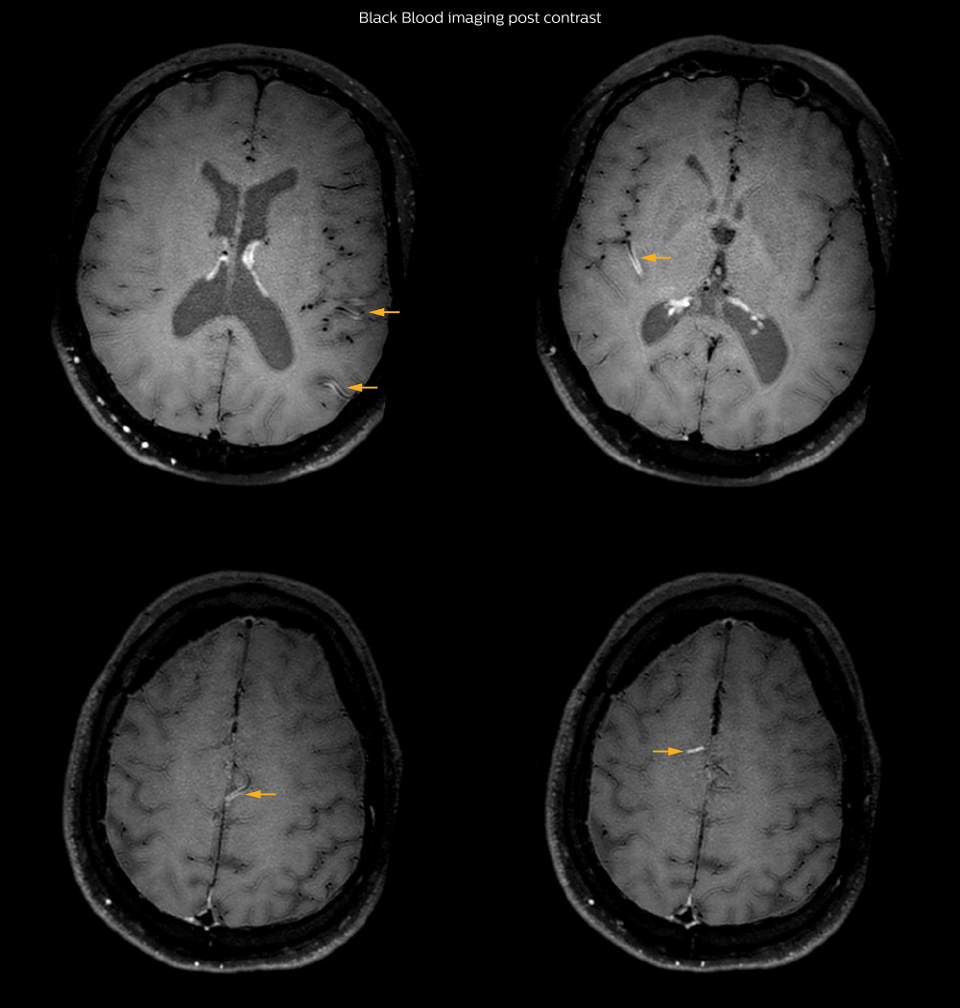

On FLAIR images we can see some nonspecific high signal abnormalities in frontal white matter bilaterally. On DWI we can see acute ischemic lesions which appear with high signal intensity. Arrows show vessel wall enhancement which appears concentric and homogeneous in different cerebral territories.

On the routine MR sequences that we did, we could see acute ischemic lesions. We see them very well on the diffusion images, where acute ischemic lesions usually appear with high signal intensity and restricted diffusion. However, the etiology of these lesions cannot be derived from these images. An area of restricted diffusion was seen in the anterior cerebral artery territory and we concluded it was an ischemic lesion. On MR angiography we can just see if there is stenosis or vessel occlusion, but it does not provide us information on the etiology of this kind of lesion. So, we decided to perform Black Blood imaging. The presence and the pattern of vessel wall enhancement on Black Blood imaging, can help us to determine the etiology of the lesion. differentiate vasculitis from other causes of vasculopathy, such as atherosclerosis, with a high specificity [1-3]. In an atherosclerotic lesion, vessel wall thickening and enhancement are usually eccentric, while in vasculitis the wall thickening and enhancement are usually concentric, homogenous, and in a long portion of the vessel. of patients whenever their treatment is installed in order to determine the efficacy of a particular treatment. In this case the Black Blood imaging helped us to suggest the diagnosis of HIV-related brain vasculitis.

Many studies have shown that Black Blood imaging can help